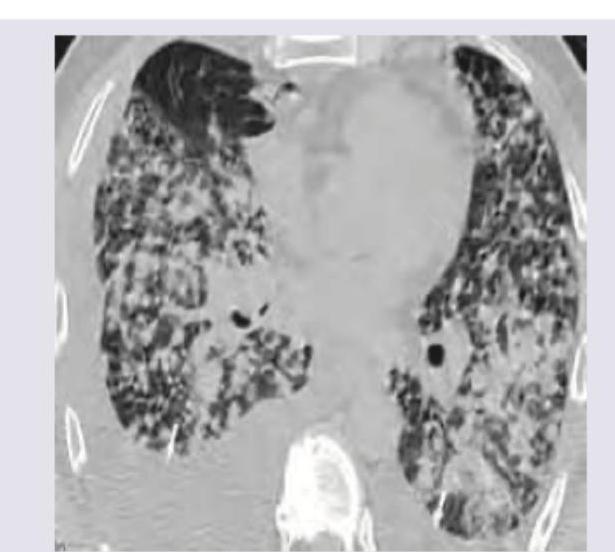

The following CT chest shows presence of:

Explanation: ***Bronchiectasis*** - The CT image shows widespread **dilated bronchi** with thickened walls, often described as a **"tram track" appearance**, which is characteristic of bronchiectasis. - There are also areas of **mucus plugging** and **honeycombing**, further supporting the diagnosis of severe bronchiectasis. - Bronchiectasis represents **irreversible dilation** of the bronchial tree, best visualized on high-resolution CT. *Pneumoconiosis* - This condition typically presents with diffuse small nodules, irregular opacities, or progressive massive fibrosis. - The imaging features in the provided CT, such as dilated airways, are not typical for pneumoconiosis. *Carcinoma lung* - Lung carcinoma usually manifests as a **mass**, **nodule**, or **adenopathy** on CT, often with associated features like pleural effusion or atelectasis. - The diffuse, cystic, and tubular changes seen in the image are not consistent with primary lung cancer. *Chronic bronchitis* - Chronic bronchitis is a clinical diagnosis defined by chronic cough with sputum production, and while it involves airway inflammation, it does not typically show the severe **structural bronchial dilation** seen in this CT. - CT findings in chronic bronchitis might include bronchial wall thickening, but not the widespread irreversible dilation characteristic of bronchiectasis.